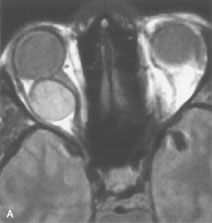

On MRI, uveal melanomas have a typical appearance that helps to differentiate them from other primary and secondary intraocular tumors as well as choroidal detachments. Pigmented melanomas are hyperintense on Tl-weighted images, hypointense on T2-weighted studies, and hyperintense on proton density–weighted examinations (Fig. 24).30,31,50,80–82 These signal characteristics have been attributed to the paramagnetic properties of melanin because of stable free radicals that shorten the T1 and T2 relaxation times. Moderate enhancement is seen on postgadolinium T2-weighted images. Gadolinium-enhanced T1-weighted images are particularly sensitive in detecting choroidal melanomas.83 MRI may be less sensitive in detecting extrascleral extension of tumor than echography performed by an experienced ultrasonographer.84

Fig. 24. A. T1- and (B) T2-weighted MR scans demonstrate a small nodular intraocular mass (arrows) that is very hyperintense on the T1-weighted scan and hypointense on the T2-weighted image. This signal intensity pattern is due to the presence of free radicals within melanin granules. C and D. Postcontrast fat-suppressed T1-weighted scans demonstrate homogeneous intense enhancement of the lesion and no evidence of seleral penetration or optic nerve invasion.